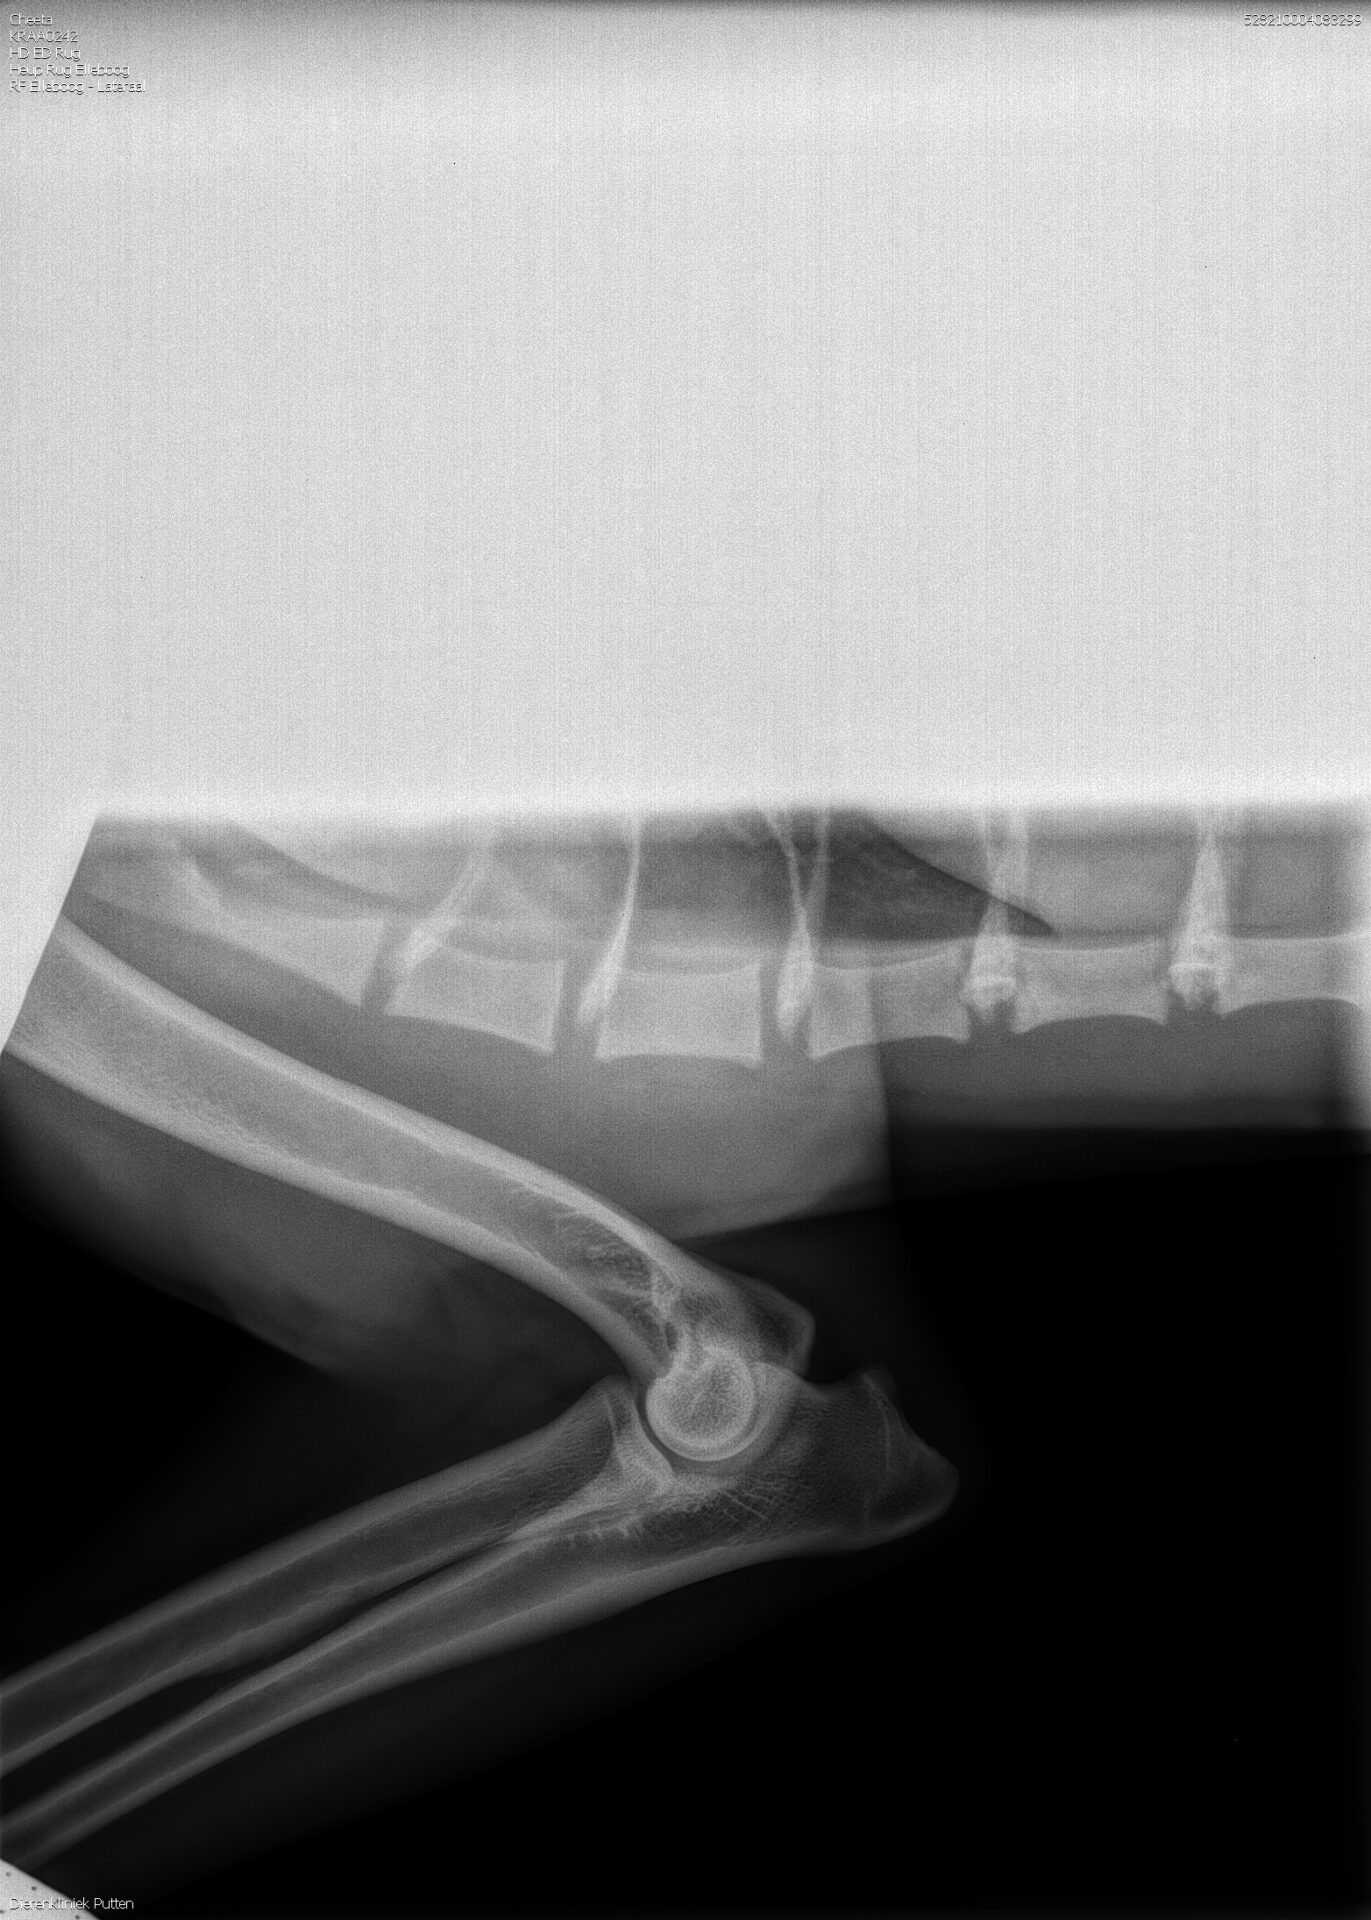

ED: vrij